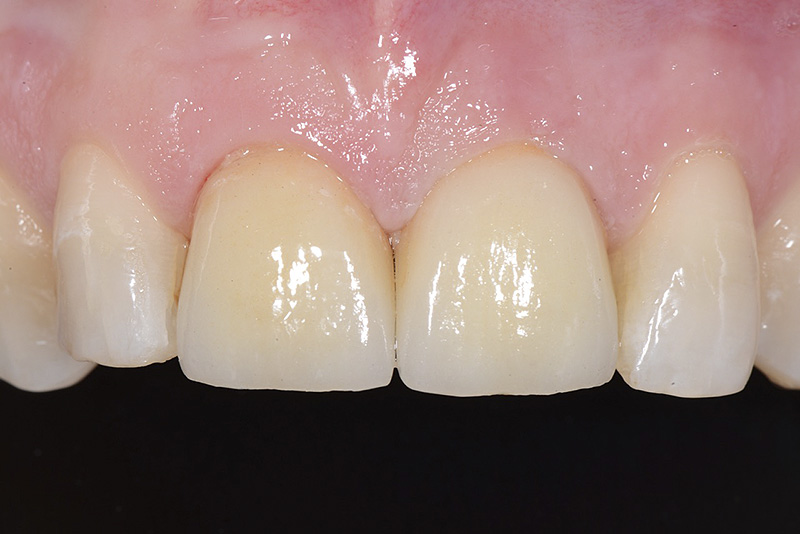

PREMESSA: in seguito all’estrazione dell’incisivo laterale superiore di destra, resasi necessaria per cause batteriche, si decide di affrontare il caso con il posizionamento di un impianto in sostituzione dell’elemento mancante dopo guarigione del sito infetto. Con tecniche rigenerative sia dei tessuti ossei mancanti a causa dell’infezione pregressa, sia dei tessuti gengivali che appaiono inizialmente troppo spostati in alto, si ripristina una corretta morfologia delle parabole (contorni) gengivali e delle papille interdentali (triangoli di gengiva tra due denti vicini).

Vengono utilizzati 2 tipi di provvisori: il primo, cementato ai denti vicini, viene utilizzato dal momento dell’estrazione del dente fino ad impianto osteointegrato (circa 6 mesi); il secondo, avvitato direttamente all’impianto, ha una funzione di prova estetica ma soprattutto di guida per la maturazione dei tessuti gengivali peri-implantari portandoli verso la maturazione completa prima di posizionare la corona finale in disilicato di litio.